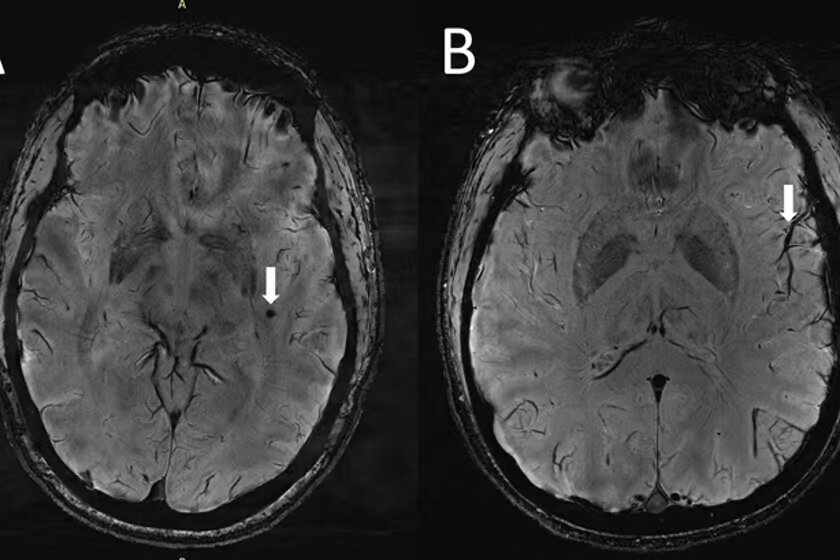

اکنون یک مطالعه با استفاده از فناوری تصویربرداری پیشرفته برای به دست آوردن دیدگاه جدیدی در مورد ساختارهای مغز انجام شده است که فضاهای بزرگ در اطراف رگهای خونی را در افرادی که از این بیماری رنج میبرند، نشان میدهد و بینش مهم جدیدی را برای این موضوع فراهم میکند.

تمرکز این مطالعه بر روی فضاهایی است که به عنوان فضاهای اطراف عروق شناخته میشوند که شکافهایی در اطراف رگهای خونی هستند که به پاکسازی مایعات از مغز کمک میکنند. بزرگ شدن این فضاها قبلاً با بیماری عروق کوچک مرتبط بود و مواردی مانند التهاب و ناهنجاری در سد خونی مغزی میتواند بر شکل و اندازه آنها تأثیر بگذارد.

از جملهی این تغییرات، خونریزیهای کوچک مغزی، همراه با بزرگ شدن فضاهای اطراف عروق در ناحیه مرکزی سِمیاُوال(centrum semiovale) در مغز مبتلایان به میگرن بود.

ژو میگوید: در افراد مبتلا به میگرن مزمن و میگرن اپیزودیک بدون هاله، تغییرات قابل توجهی در فضاهای اطراف عروق ناحیهای از مغز به نام centrum semiovale وجود دارد. این در حالی است که این تغییرات تاکنون هرگز گزارش نشده بود.